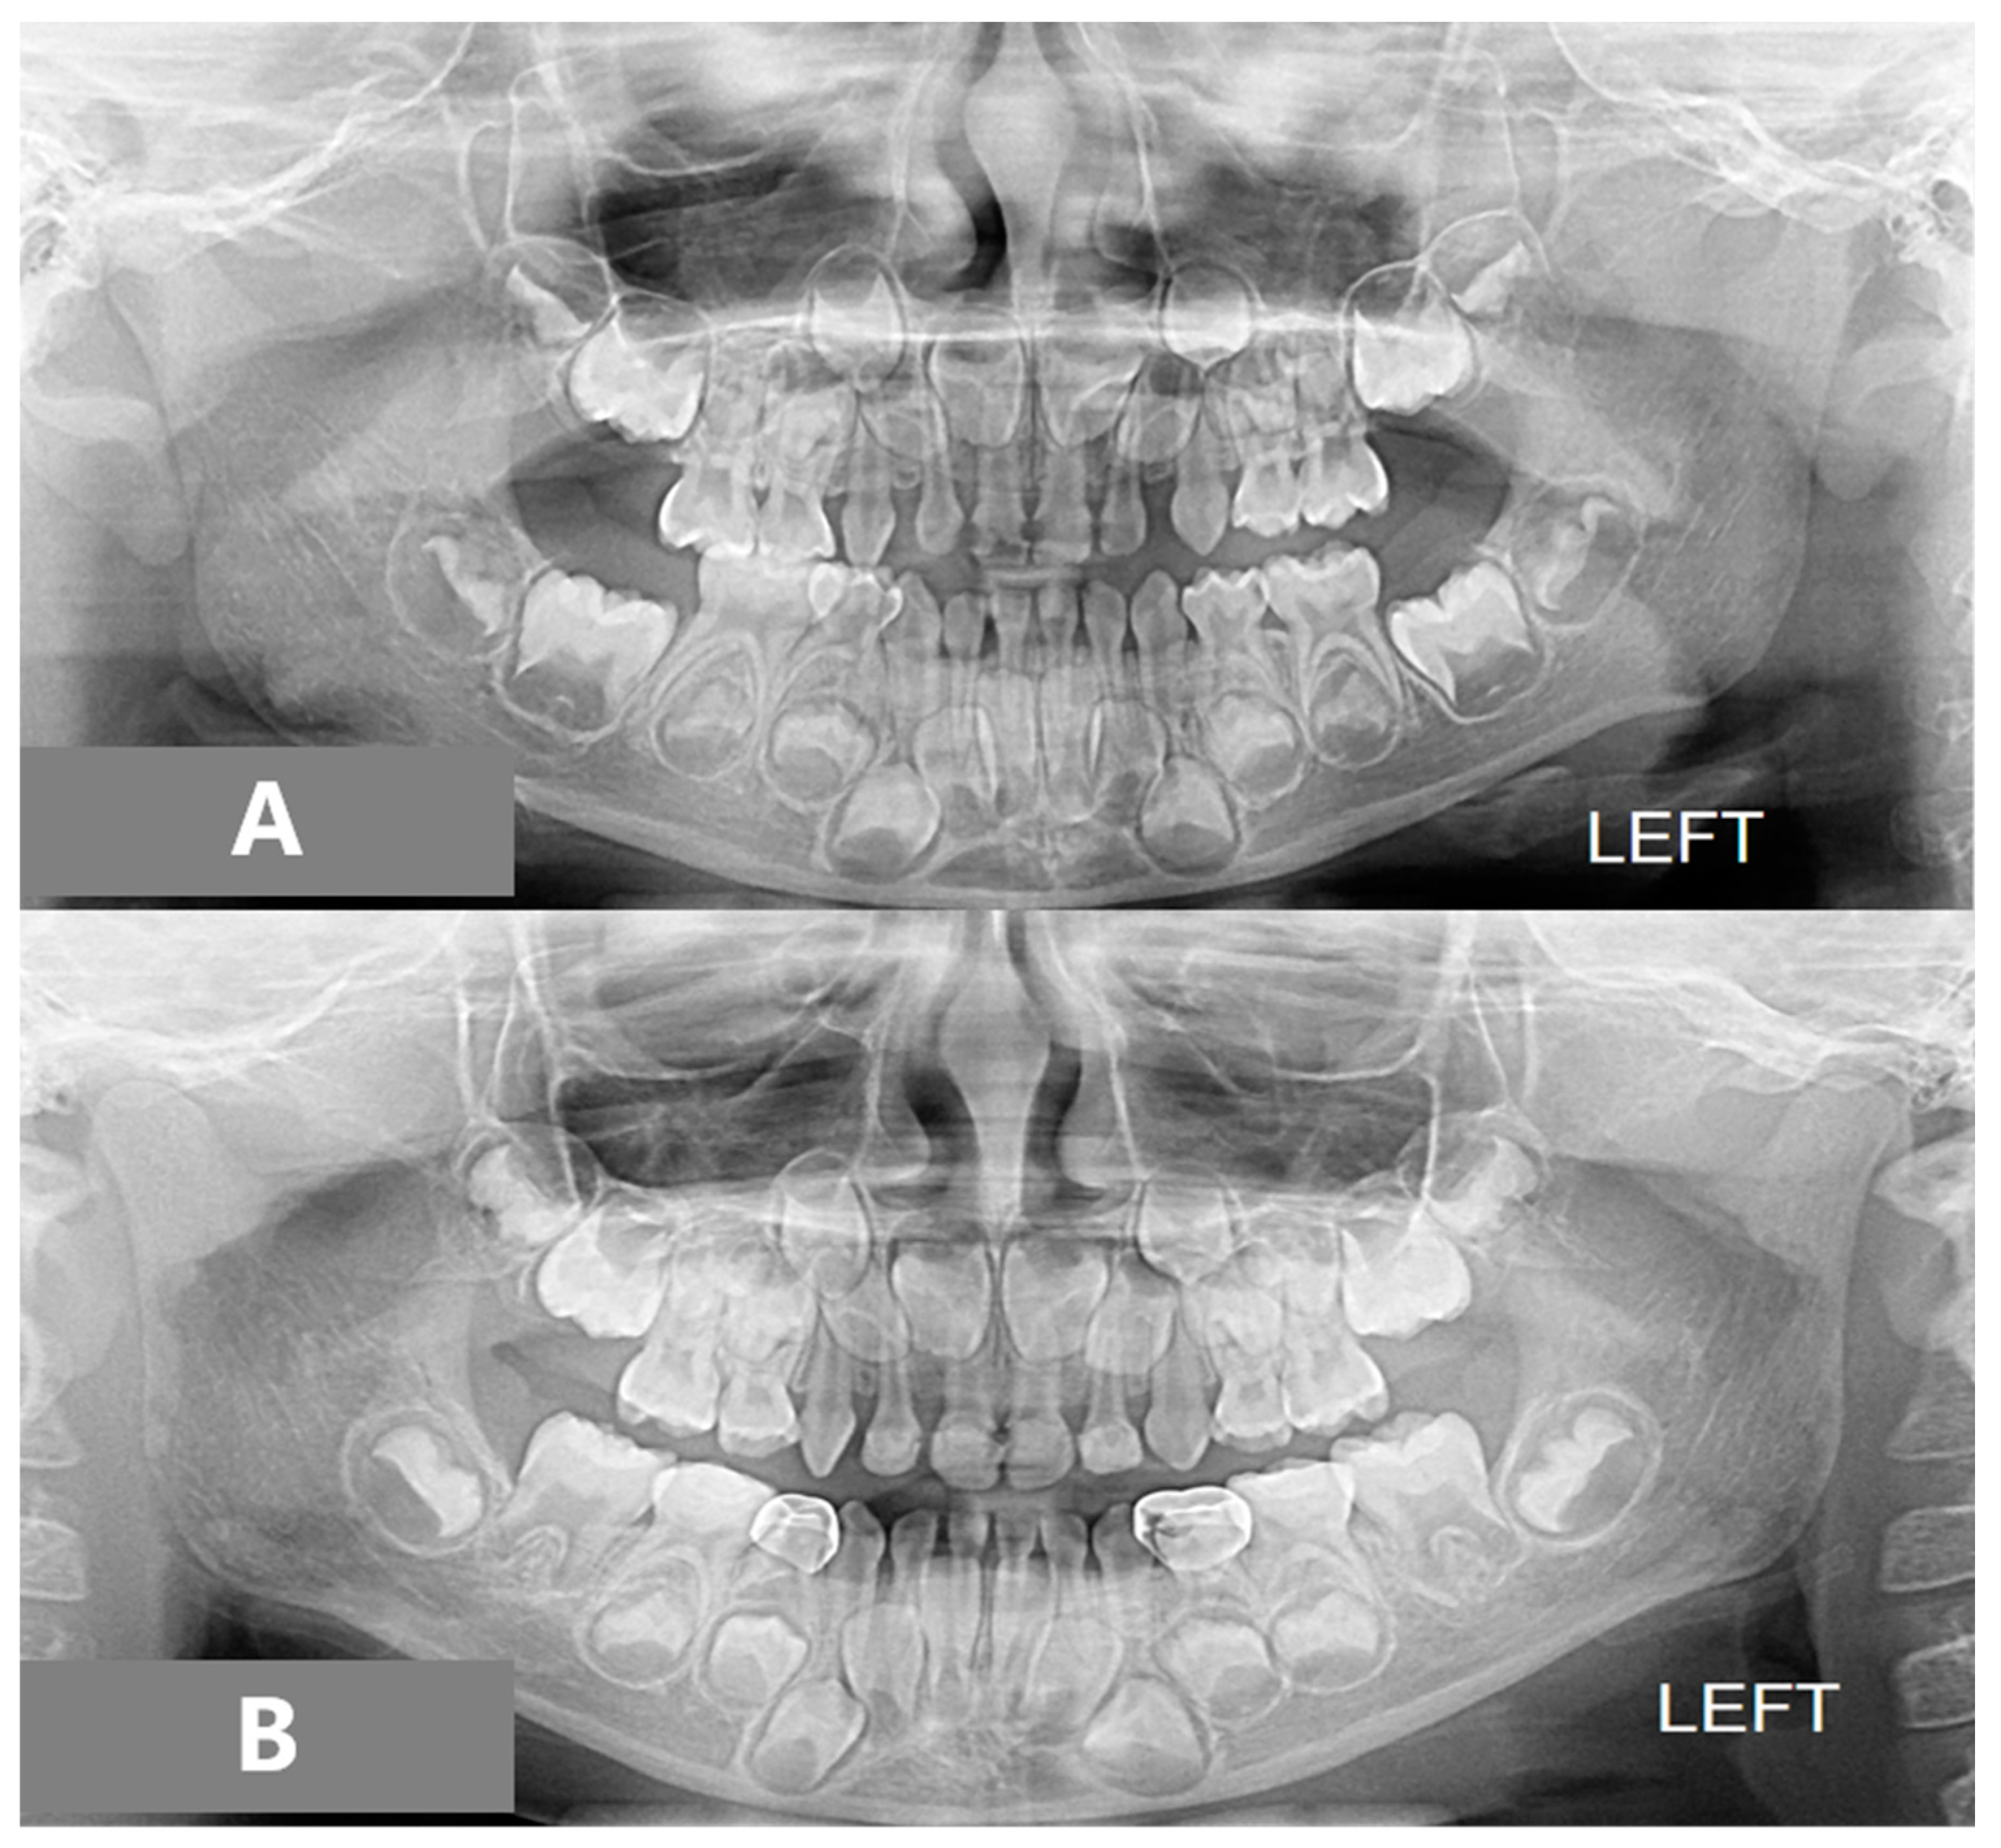

2.2. Assessments

3. Results